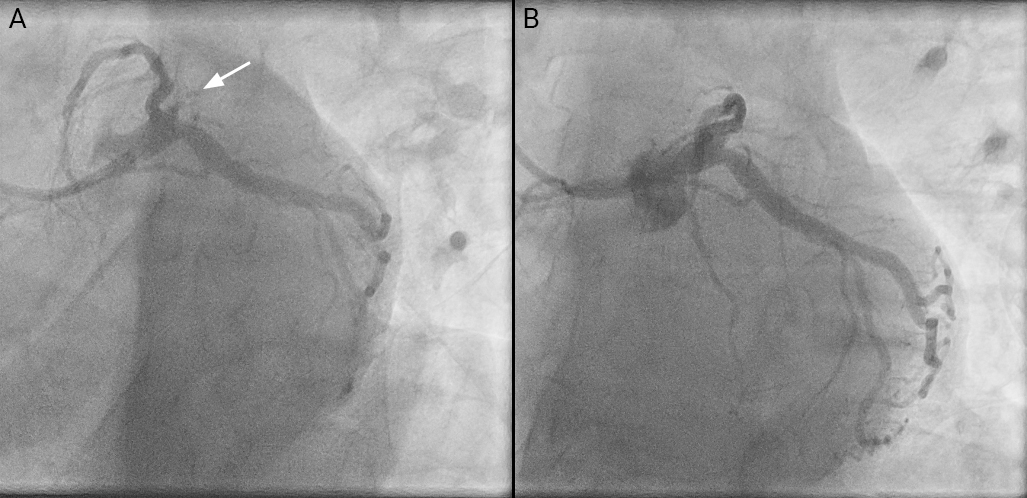

A 44-year-old man with a background of hypertension and paraplegia presented with acute chest pain radiating to the left arm, which woke him from sleep. He called for emergency medical assistance, and an ECG, performed by paramedics, showed ST-segment elevation in leads aVL and V2 and ST-segment depression in leads II, III and aVF. This ECG pattern (figure 1A) forms what has been labelled as the ‘South African flag’ pattern (figure 1B), and it is associated with high diagonal or intermediate artery occlusion.1 Urgent coronary angiography was undertaken via right radial approach and showed acute occlusion at the ostium of the intermediate artery. This was only visible with a very steep left anterior oblique (LAO) (40 degree) caudal (40 degree) view (white arrow, figure 2).

Percutaneous coronary intervention (PCI) was undertaken using a Fielder XT-A wire introduced via a 6F EBU 3.5 guide and a 2 mm semi-compliant balloon to restore flow. Intravascular ultrasound showed the intermediate to be 4 mm in diameter proximally with predominantly fibrous plaque and minimal calcification at the site of occlusion. There was diffuse disease elsewhere in the vessel, which was treated with cutting balloon then non-compliant balloon angioplasty, followed by drug-eluting stent implantation, and further treatment with a paclitaxel-coated balloon to the ostium, avoiding interference of the left main stem (LMS) trifurcation with a metallic stent. Post-procedure angiography confirmed normal flow in the treated vessel with no significant residual stenosis, and complete resolution of chest pain and ST-segment changes.